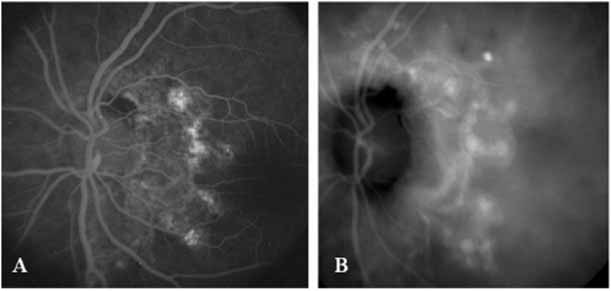

Sorenson and colleagues31 reported on the diagnostic and therapeutic ability of ICG angiography in patients who had clinical signs of recurrent CNV but who were found to have occult membranes on fluorescein angiography. In a group of 66 patients, 97% were identified as having localized areas of hyperfluorescence on ICG angiography consistent with recurrent CNV (Fig. 7). In laser photocoagulation treatment performed in a subgroup of 29 patients, 62% achieved anatomic resolution and stabilization of the exudative process over time. Visual acuity improved in 66%, 45% of whom achieved a visual acuity of 20/100 or better.

Unlike fluorescein angiography, however, ICG angiographic studies have pointed out that certain principles of laser photocoagulation treatment may not hold with this new imaging capability. This is particularly true with the concept that all areas of CNV need to be obliterated to achieve a successful anatomic result. A careful evaluation of ICG angiograms in some patients with occult CNV has revealed that two forms of neovascular lesions may exist: (1) localized, intensely hyperfluorescent leaking areas of “active” CNV; and (2) more subtle and larger areas of hyperfluorescence with minimal leakage, representing “quiescent” portions of the neovascular complex (Fig. 8). A pilot study by Guyer and colleagues22 demonstrated that localized photocoagulation treatment applied to the active area of CNV alone might result in successful and long-term anatomic stabilization and improvement in the visual acuity in some patients (Fig. 9). A subsequent review of these lesions has demonstrated that they may represent a subpopulation of occult CNV known as polypoidal choroidal neovascularization, described later.